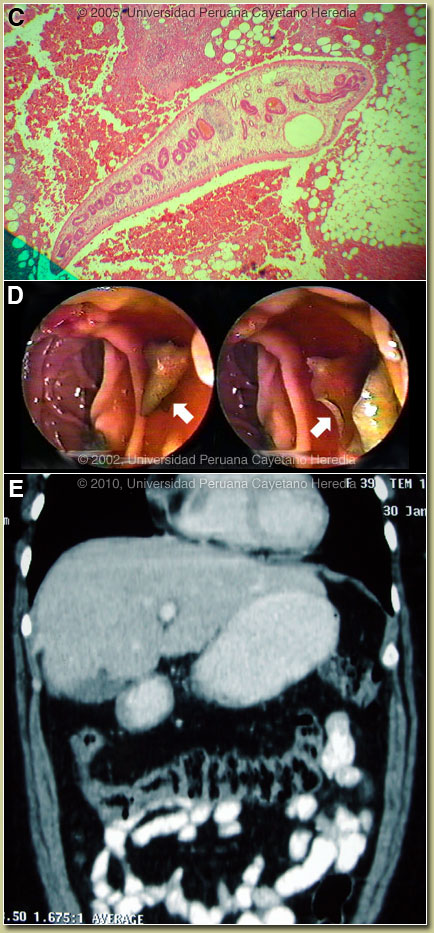

| Diagnosis: Subcapsular hematoma due to Fasciola hepatica infection, acute phase. |

Fasciola hepatica is a trematode (fluke or flatworm) in which the mature adult parasites inhabit the large biliary ducts. As with all other trematodes, Fasciola hepatica requires a snail intermediate host. Eggs produced by the hermaphroditic adults pass with the feces and hatch, releasing larvae in fresh water. After passing through a snail, mature cercariae emerge and rapidly encyst on various kinds of aquatic vegetation such as watercress. After ingestion by a human or animal definitive host, the metacercariae excyst in the duodenum and larvae penetrate the intestinal wall and subsequently directly into the liver via Glisson’s capsule embarking on a destructive migratory process through the hepatic parenchyma [Image C] for 3-4 months until they reach large biliary ducts where they mature to adults. As in this case, migration through a capsular vessel may result in significant hemorrhage. The mature adults are from 1-3 cm long and attach to the biliary epithelium by a single ventral sucker [Image D from our case files shows an endoscopic view of an adult in the common bile duct use]. In the absence of direct visualization of adults, characteristic eggs can be seen on stool examination, but more often patients present in the early migratory phases of infection prior to maturation of the worm and the onset of egg-laying. Specific serology is the test of choice. The distribution of Fasciola hepatica is cosmopolitan, but is by far the most common in sheep-raising areas where herbivores are common definitive hosts. Heavily infected sheep develop “sheep liver rot”. Other important definitive hosts are goats, cattle, horses, llamas, vicunas, and camels. The contiguous Altiplano regions of the Peruvian and Bolivian Andes are highly endemic, with human prevalence rates of as high as 67% in some villages. Egypt, Cuba, and Northern Iran are also highly endemic and the parasite is emerging in Vietnam and Cambodia. Cooking, which would kill the metacercariae, dramatically changes the flavor of watercress and the population is reluctant to adopt this simple measure. Our patient regularly ingested emoliente, a local tea-like drink that uses drops of watercress juice to provide a bitter flavor. Clinically, the disease can be divided into acute and chronic phases. During the acute phase, migrating parenchymal larvae generally cause fever, eosinophilia, right upper quadrant pain and especially significant anorexia. Vomiting and weight loss of 20 kg or more may develop, which usually abates when the larvae mature to adults. The adult flukes in the biliary tree are generally asymptomatic but some patients develop chronic manifestations including right upper quadrant pain, nausea, vomiting, and hepatomegaly. Eosinophilia and abnormal liver function may develop but are less common than with acute disease. Adult flukes may cause hyperplasia, desquamation, thickening, and dilatation of the bile ducts. Malignant degeneration and cholangiocarcinoma such as results from chronic infection with the oriental liver fluke Clonorchis sinensis has not been reported with Fasciola hepatica. We have recently reported a case series with clinical findings and evolution of disease [Am J Trop Med Hyg. 2008;78:222-7]. Please see Gorgas Case 2005-02 for a CT image of the typical larval tracks seen in acute disease. The differential diagnosis of eosinophilia with accompanying destructive hepatic lesions is limited. Toxocariasis causes hypereosinophilia with hepatomegaly but the pathology results from small granulomas around individual non-migrating larvae and not the large destructive lesions seen in our patient. Eosinophilia is common in Perú so it may be due to an unrelated event present concomitantly with a bacterial liver abscess; this had been the initial impression in this case. Fasciola hepatica is the only trematode infection for which praziquantel is not the drug of choice. WHO has put the anthelmintic triclabendazole (Egaten, Novartis) on its essential drugs list. Egaten is registered in Perú (as in Mexico and Egypt) and is available via free donation from the WHO. In the U.S. and many other countries Egaten can be obtained by special release from the manufacturer or it may be obtained directly from the World Health Organization in Geneva. The usual dosage is 10mg/kg with a meal. Many practitioners repeat the dosage 12-24 hours later. In our institute the cure rate is 96% [A. Terashima, unpublished]. Our patient was treated with a single 10 mg/kg dose of triclabendazole and has subsequently had 4 negative stool O & P examinations. When seen by the Gorgas participants 1 year after her diagnosis, the patient was asymptomatic with 4% eosinophils, negative stool exam, and negative ELISA. A follow-up CT scan is shown with resolution of the hematoma [Image E]. |